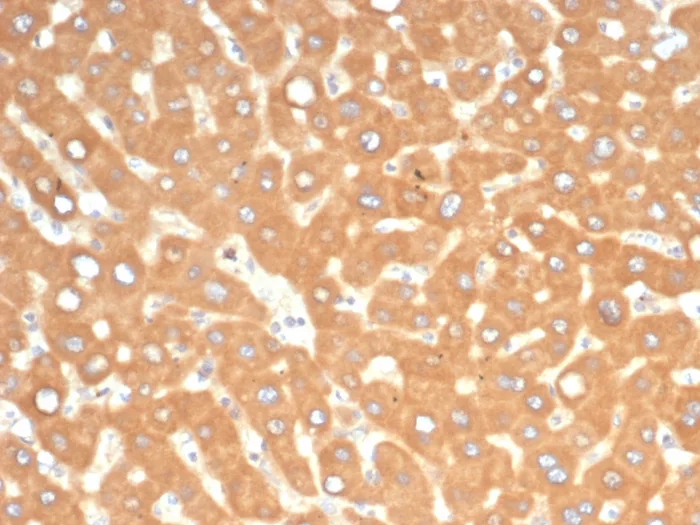

Formalin-fixed, paraffin-embedded human liver in colon stained with EPH Receptor B4 (EPHB4) Mouse Monoclonal Antibody (EPHB4/6391). HIER: Tris/EDTA, pH9.0, 45min. 2°C: HRP-polymer, 30min. DAB, 5min.